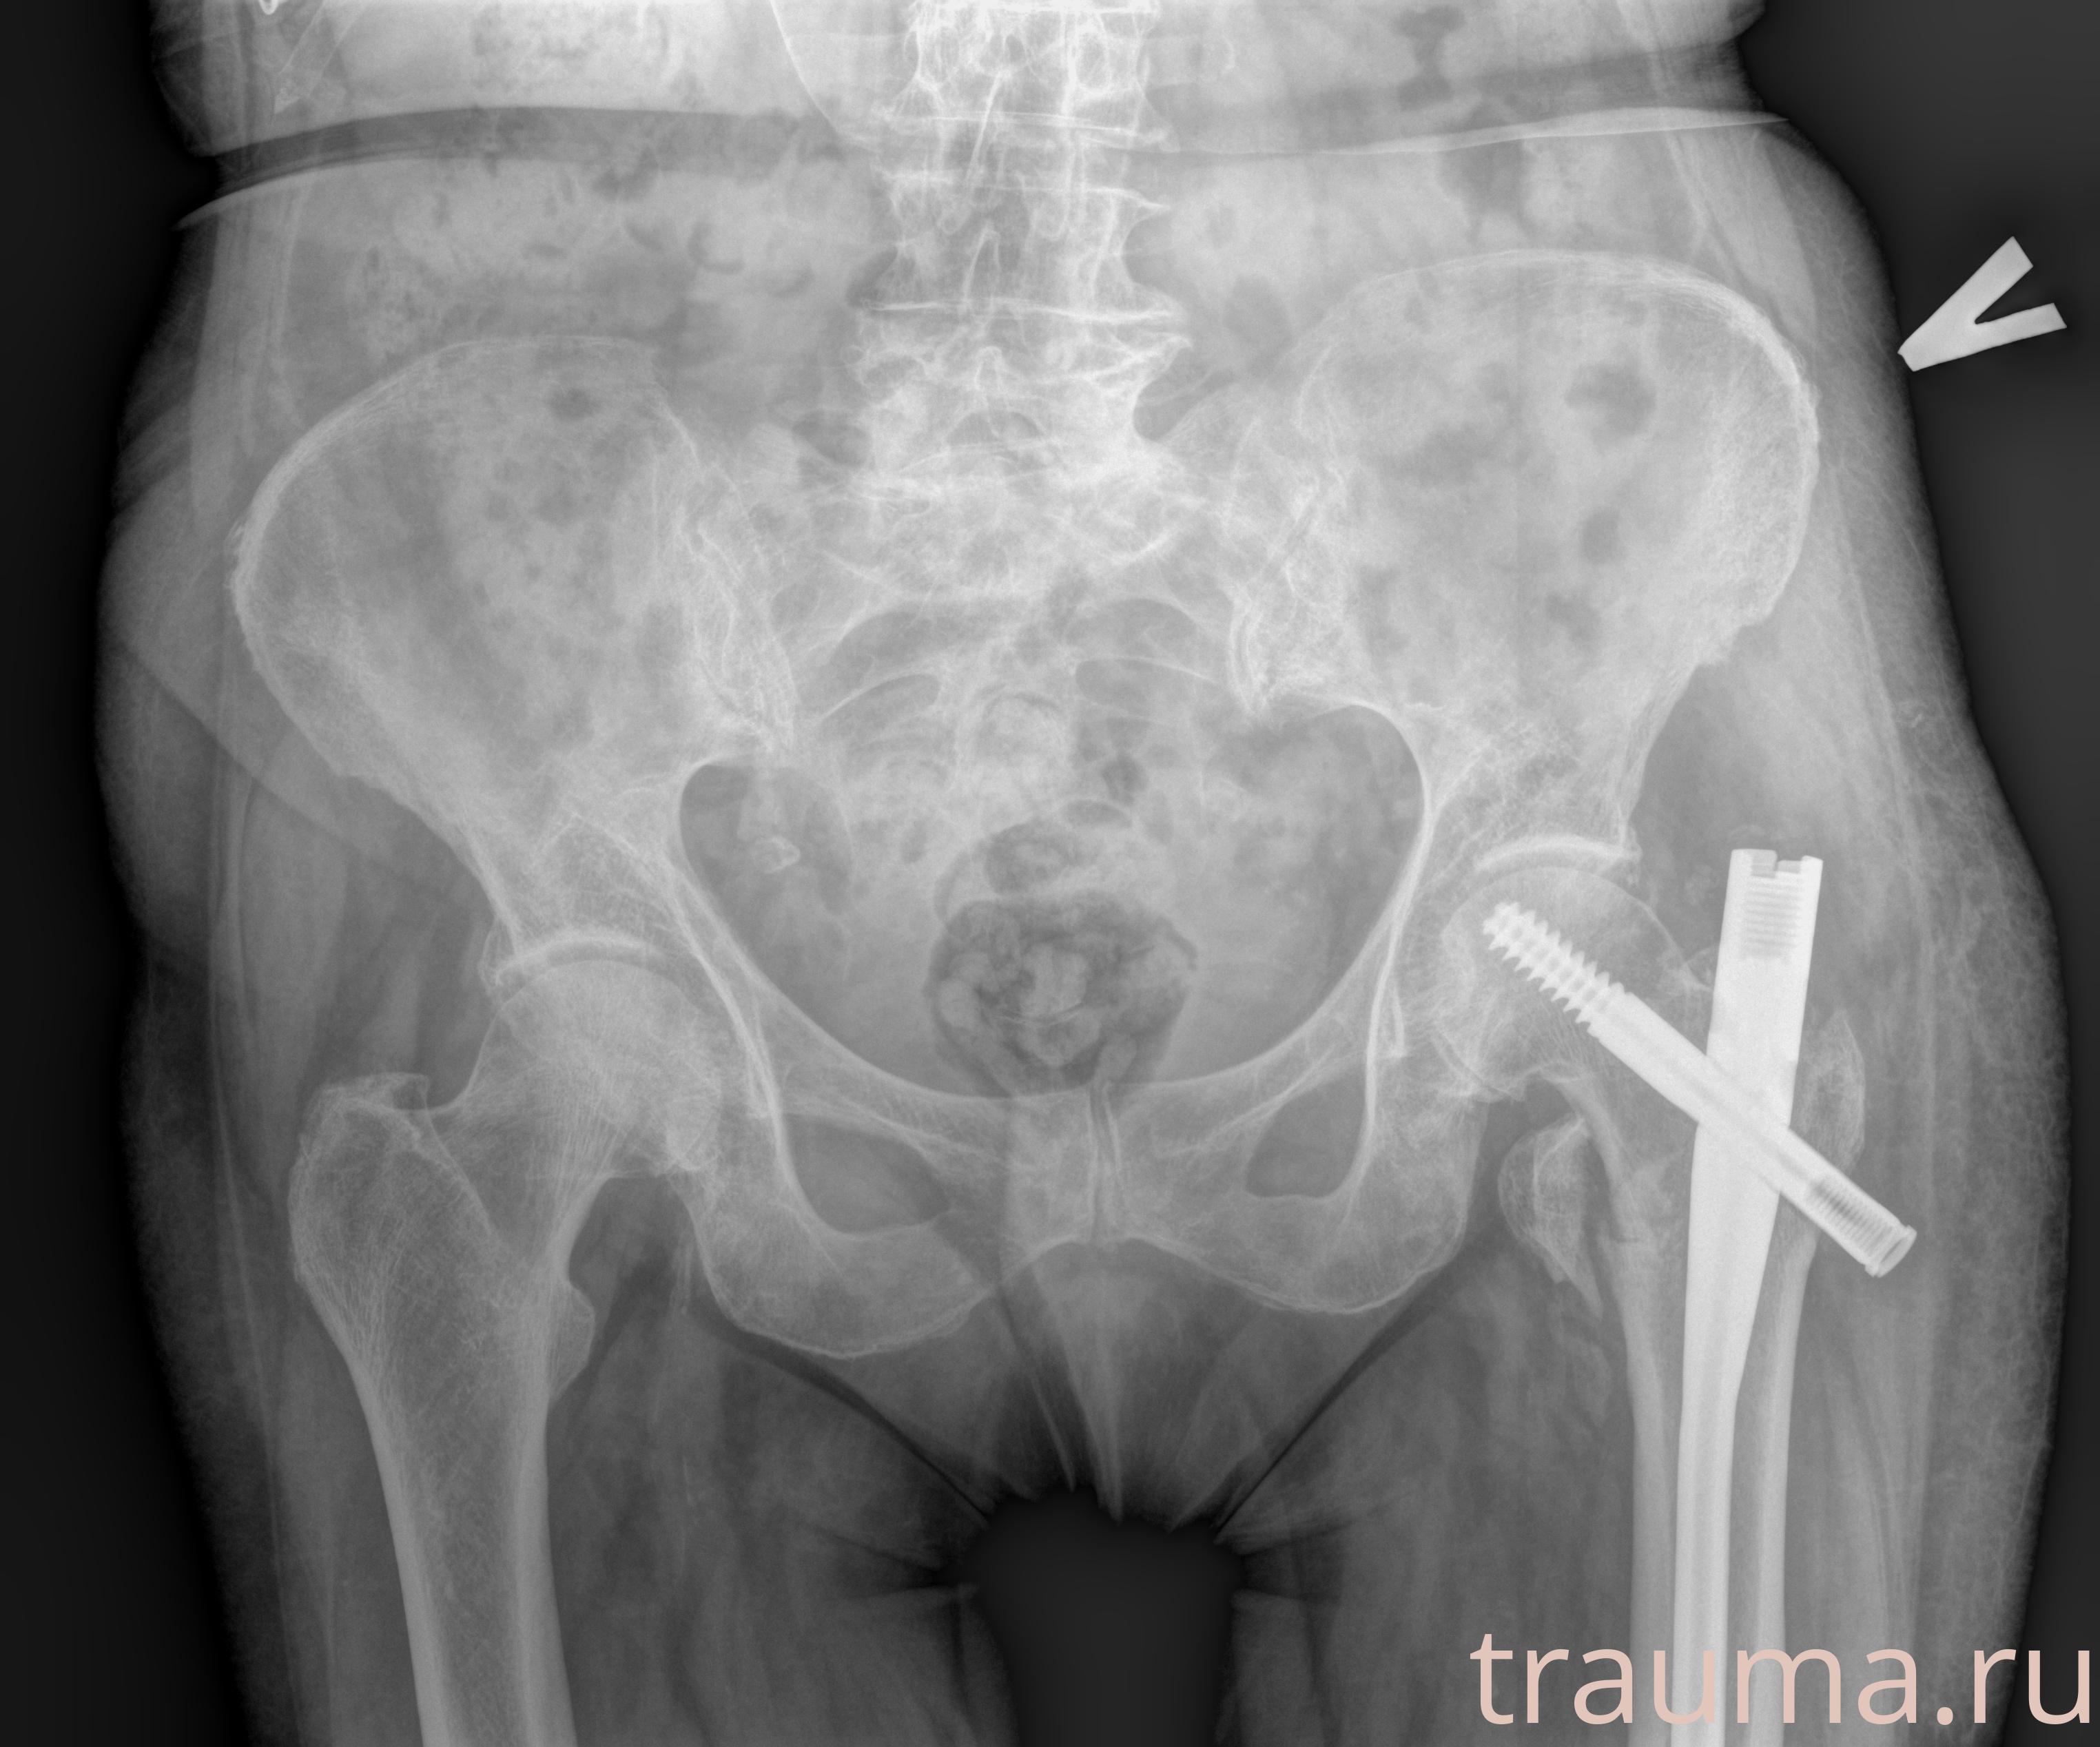

Рентген на дому: по вашему адресу приезжает врач-рентгенолог, травматолог-ортопед с мобильным рентгеновским аппаратом, проводит диагностику травмы или заболевания, делает необходимые рентгенограммы, дает рекомендации по дальнейшему лечению. Получить качественные снимки в домашних условиях возможно благодаря уникальной методике, разработанной МосРентген Центром для института  Склифосовского